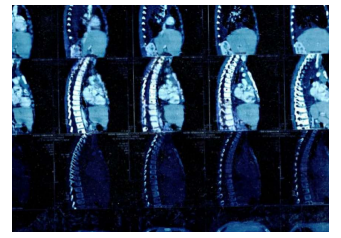

MRI showed: a mass in the posterior mediastinum surrounding the tracheal branch and reaches the diaphragm, surrounding the Azygos vein, superior vena cava, aorta, major vessels and esophagus, measuring (11*5*7) cm. and foci osteolysis in the 9,11,12 thoracic vertebrae.